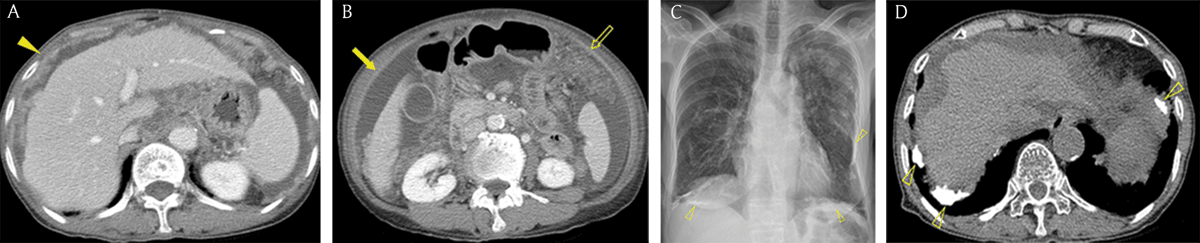

Figure 3

Common seeding sites in peritoneal carcinomatosis. (A–E) Axial portal venous phase CT images show the frequent locations for peritoneal seeding (arrows): peritoneal reflexion (A), lower small bowel mesentery (B), sigmoid mesocolon (C), right paracolic gutter (D), right subphrenic space (E), and greater omentum (F).